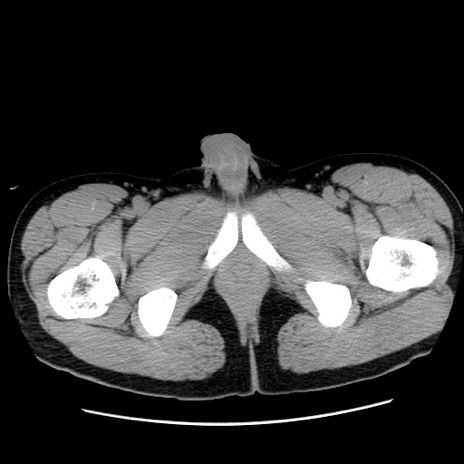

症例36(横断像)

【症例】20歳代 男性

【主訴】心窩部痛

【現病歴】今朝より上腹部痛あり。一旦軽快していたが再度出現したため救急要請。昨日夕に白身の魚を含む刺身を食べた。

【身体所見】BP 136/89mmHg、HR 74/min、BT 37.0℃、腹部:膨満、軟、心窩部に圧痛あり。反跳痛なし、筋性防御なし、腸雑音やや亢進あり。

【データ】WBC 17700、CRP 0.48